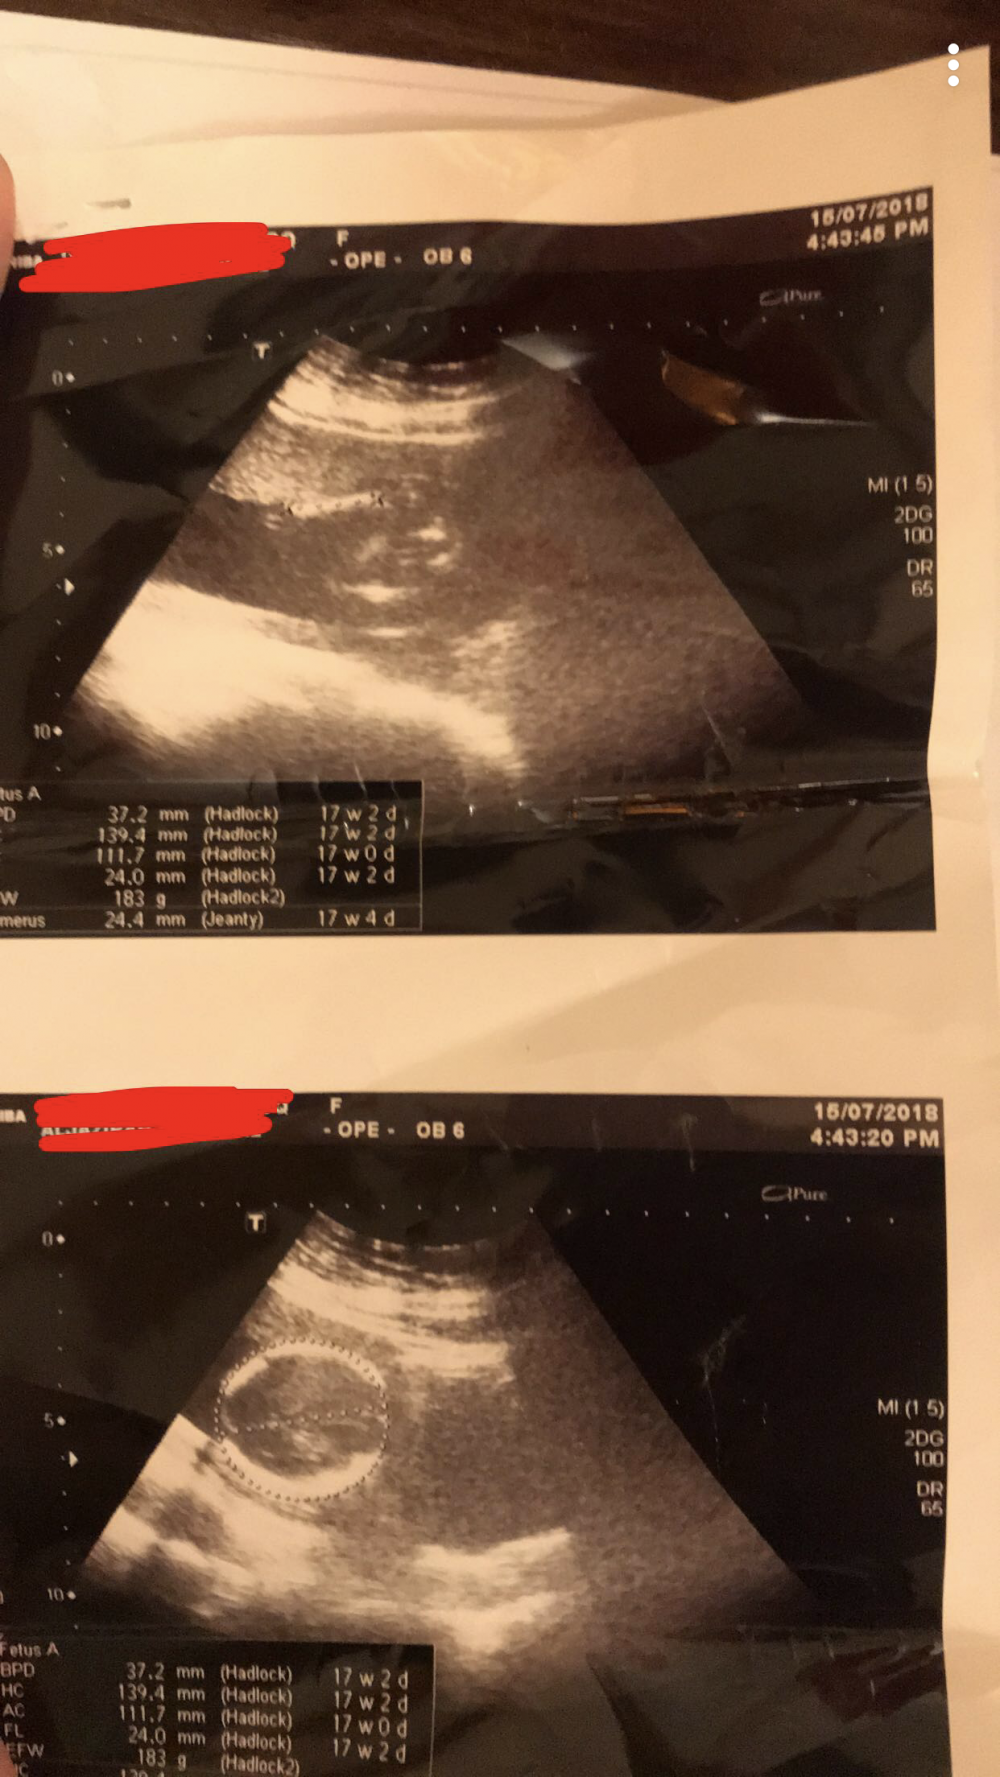

اللي متضح لي بنت شوفي ثاني صوره فيه خطين وخط بالنص شكل الهبمرجرر هذي بنت بس بالخامس تاكدي افضل

اللي متضح لي بنت شوفي ثاني صوره فيه خطين وخط بالنص شكل الهبمرجرر هذي بنت بس بالخامس تاكدي افضلاللي متضح لي بنت شوفي ثاني صوره فيه خطين وخط بالنص شكل الهبمرجرر هذي بنت بس بالخامس تاكدي افضل

انا بالسابع الحين رحت بالسادس بس قالت مو واضح 😓

هل ممكن يكون اسبوع ١٧ بدري ولا يوضح او كيف ؟!